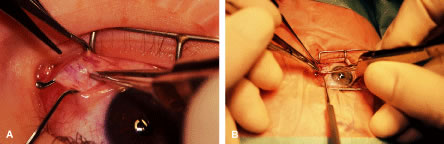

RECESSION PROCEDURE: FORNIX INCISION

This procedure is recession of the right medial rectus muscle. The eyelids are separated with a Barraquer open-blade wire eyelid speculum (Fig. 8). The open-blade design provides more room for exposure and makes it easier to pass the suture needles, especially in small children or when large recessions are performed. The globe is grasped with a Lester forceps at the limbus. It is best to grasp the limbus with the forceps held perpendicular to the globe and then to position the forceps so that they are rotated and lie tangential to the globe. Forced ductions are performed to detect any restriction of movement of the globe (Fig. 9).

|

The globe then is gently elevated from the orbit or proptosed at the same time it is abducted or adducted to prepare for the incision. Elevation of the globe helps to separate the horizontal rectus muscle from the inferior rectus muscle so that the inferior rectus muscle is not cut when the incisions are made. The conjunctiva is grasped by the assistant with a Manhattan toothed forceps (Fig. 10). This forceps has teeth that are angled outward and are designed to grasp conjunctiva, as well as the deeper subconjunctival tissue, so that when the blunt-tipped Westcott scissors cuts into the tented tissue, an incision is made into the conjunctiva and Tenon's capsule (Fig. 11A and B). If the incision does not completely penetrate Tenon's capsule and the intermuscular septum to the scleral surface of the eye, additional tissue (anterior Tenon's tissue and/or intermuscular septum) is grasped with the Manhattan forceps and at least one additional cut is made.